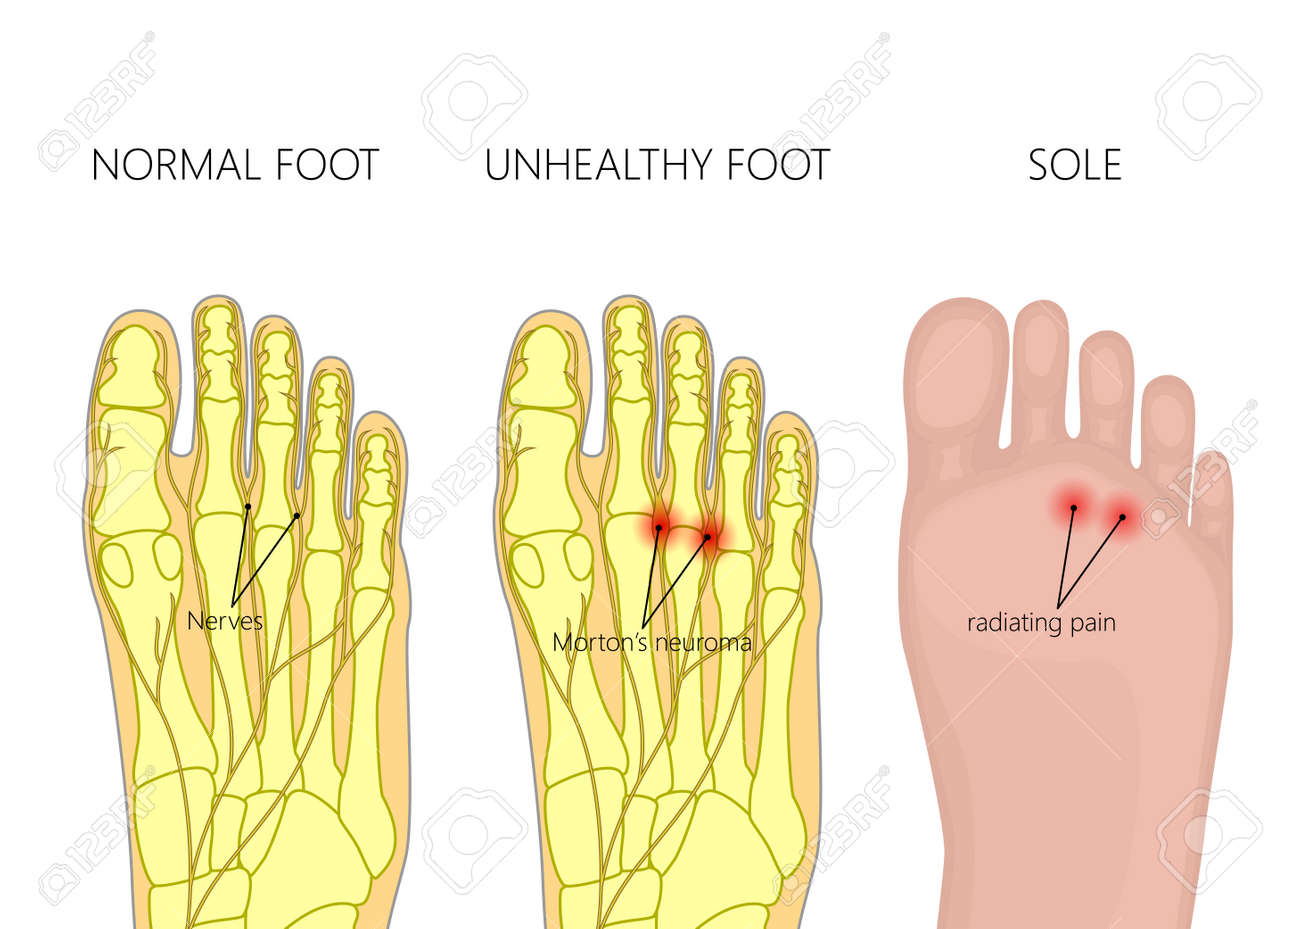

Morton Neuroma Pathology

Morton Neuroma Pathology / Troy watson, m.d., serving henderson nv, las vegas nv and the surrounding area.